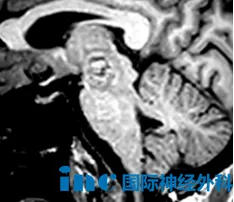

59岁的周女士因右侧丘脑-中脑右侧出血性病变,考虑海绵状血管畸形可能,出现右眼不能睁开、视物重影、视野受限伴左侧肢体肌力下降。保守治疗后症状部分缓解,但仍存在右眼上睑下垂,复视,视野受限,左侧肢体无力,且病变面临再出血风险。

面对脑干区手术的高风险与不确定性,周女士与家人一度陷入焦虑与犹豫。在寻求多名专家意见后,一次契机让他们了解到国际脑干手术专家巴特朗菲教授。巴教授在详细分析影像资料后明确指出,病变位于中脑内侧被盖区的动眼神经核核心区,且侵犯第三脑室室管膜,再出血风险极高,手术指征明确。他强调:“此类血管瘤一旦全切,预后通常非常好。我之前已成功处理过多例类似病变,并多次发表了相关研究成果。如果患者决定接受手术,全切也是我们的目标。”